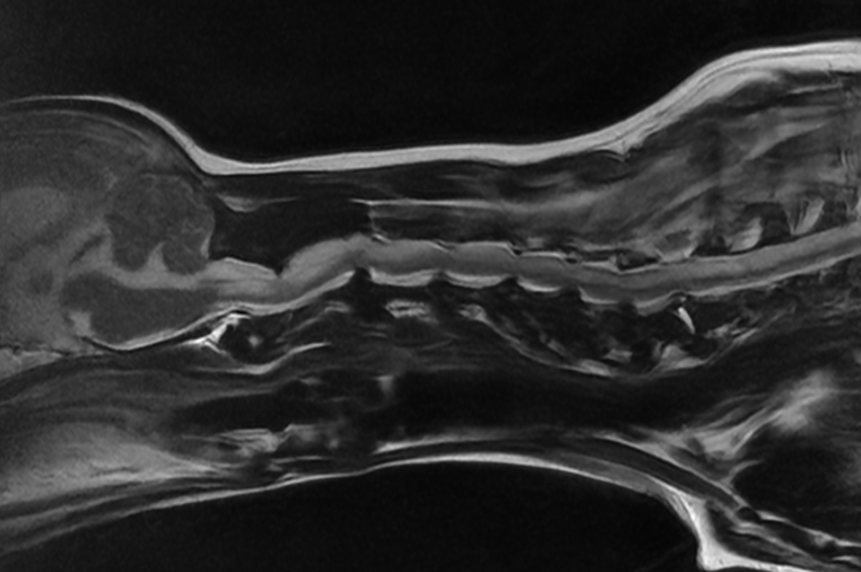

• MRI 결과

MRI에서는 아래의 복합 병변이 모두 확인되었습니다.

MRI 검사 결과 / 출처: 온숲동물의료센터

craniocervical anomaly(두개·경추부 기형)

뇌에서 척수로 이어지는 출구가 선천적으로 좁은 상태라 뇌와 신경줄기를 #강아지척수고계속 압박하고 있는 구조

AA band

뇌 뒤쪽 공간을 누르면서 뇌척수액 흐름을 방해하는 얇은 밴드 같은 조직이 있어 신경 압박을 더 심하게 만드는 요소

COMS(Caudal Occipital Malformation Syndrome)

후두골이 비정상적으로 형성되어 뇌줄기 주변을 압박하는 기형

Hydrocephalus(뇌수종)

뇌척수액이 원활하게 빠져나가지 못하면서 뇌 안에 물이 점점 차 압력이 증가하는 상태입니다.

Syrinx(척수 공동증)

척수 내부에 액체가 고여 빈 공간(공동)이 생겨 신경 기능이 떨어지고 통증이 발생하는 상태

Cervical IVDD(경추 디스크 질환)

목뼈 사이 디스크가 튀어나와 신경을 자극하거나 압박하는 질환

즉, 구조적 기형 + 척수 병변 + 디스크 질환이 동시 존재하는 고난도 신경질환이었습니다.